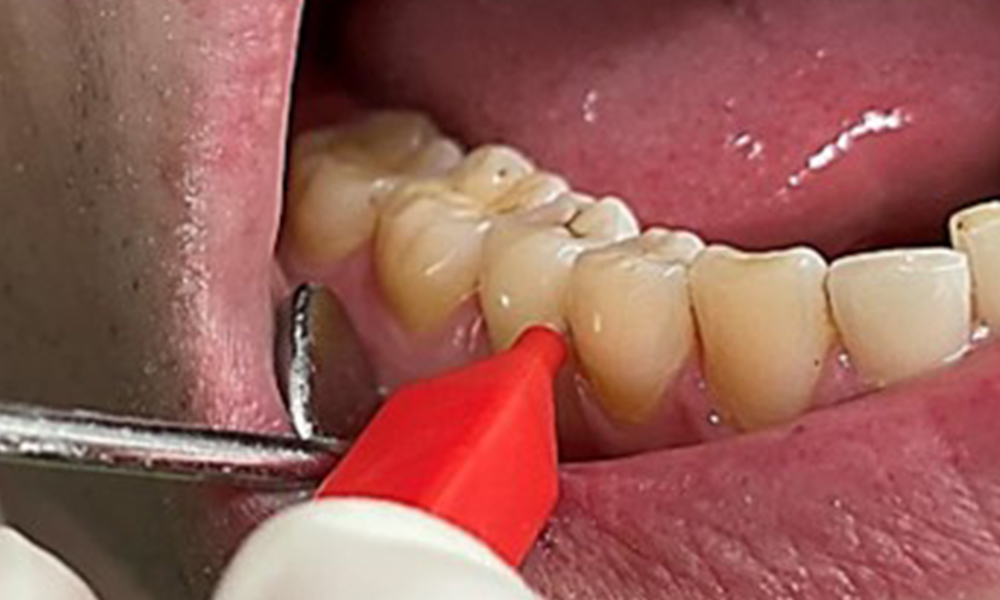

Instruction and motivation are important components of these appointments. Good home-based intraoral hygiene behaviour and understanding are important for patients. Plaque accumulation is particularly evident in the cervical regions (Fig. 8).

These must be discussed with the patient, and improvements to the teeth-brushing technique must be practised. A soft toothbrush attachment is recommended for home-based intraoral hygiene due to the presence of erosions and attritions.